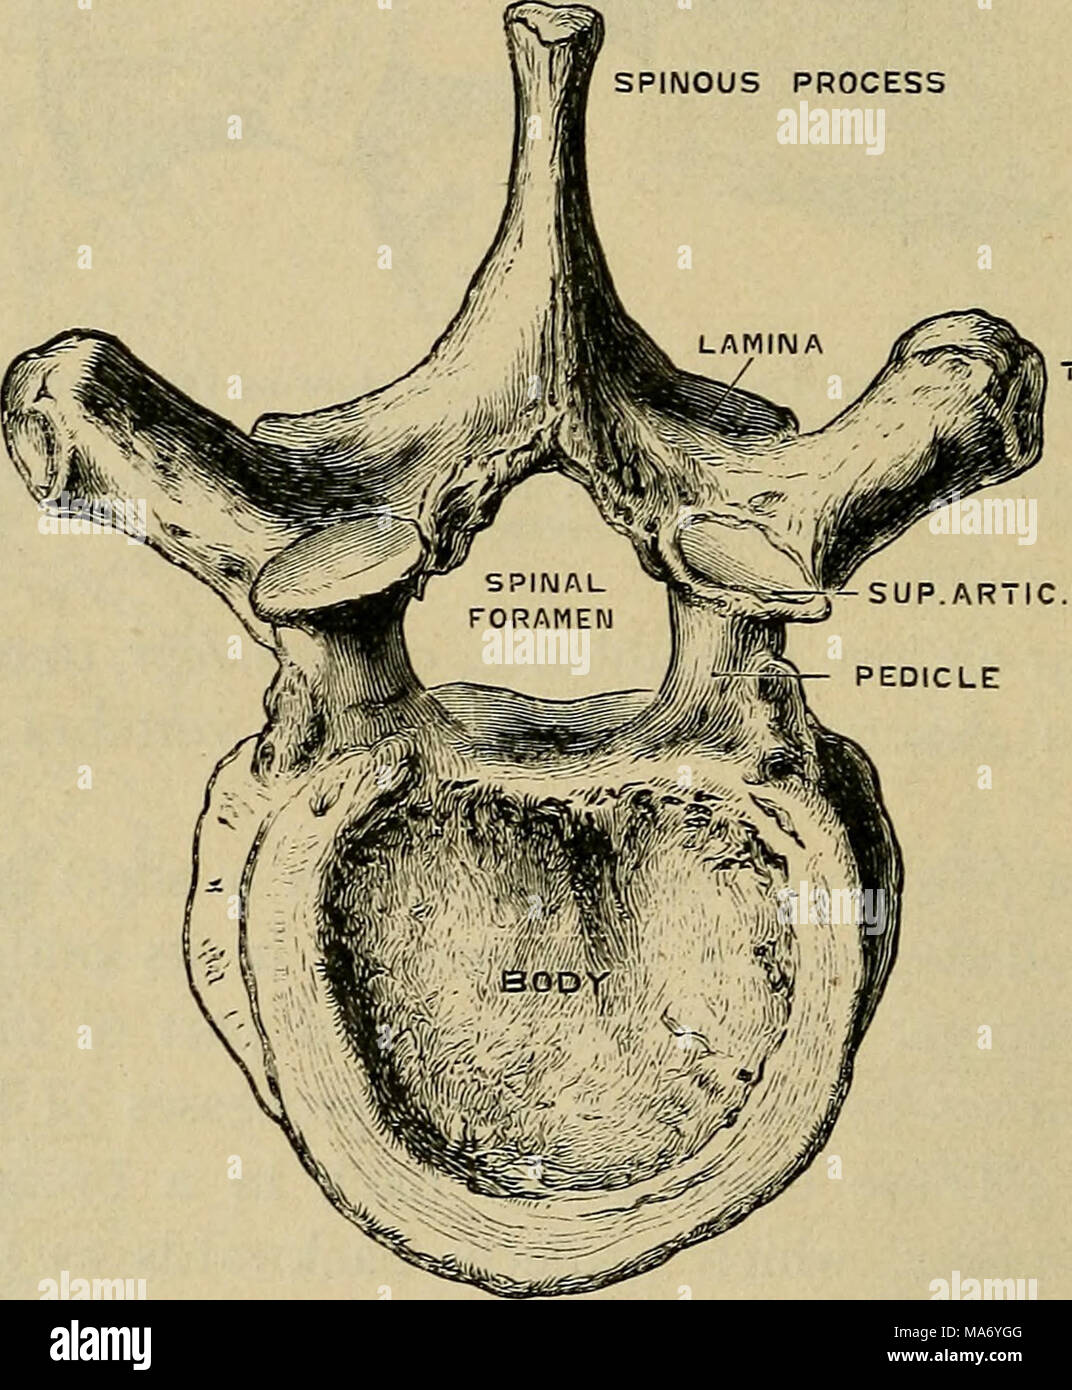

RMMA6YGG–. Fisiologia elementare . Processo RANSVERSE ^SUP AR7IC.processo peduncolo Fig. 8.-decima vertebra dorsale, dall'alto. (Disegnata da D. Gunn.) nel caso di tali vertebre per cui le nervature sono allegate (dorsale vertebrse), ciascuno di questi processi trasversali porta una piccola faccetta articolare, per cui un simile aspetto sul corrispondente nervatura è applicato. Sui corpi di questi stessi vertebrse dorsale al di sopra e al di sotto di ogni lato vi è una metà sfaccettatura, che in ogni caso si congiunge con il suo prossimo nella vertebra più vicina per fare tutta una sfaccettatura, per l'articolazione con la testa della costola. In modo tale che ciascuna nervatura ha due punti di interesse